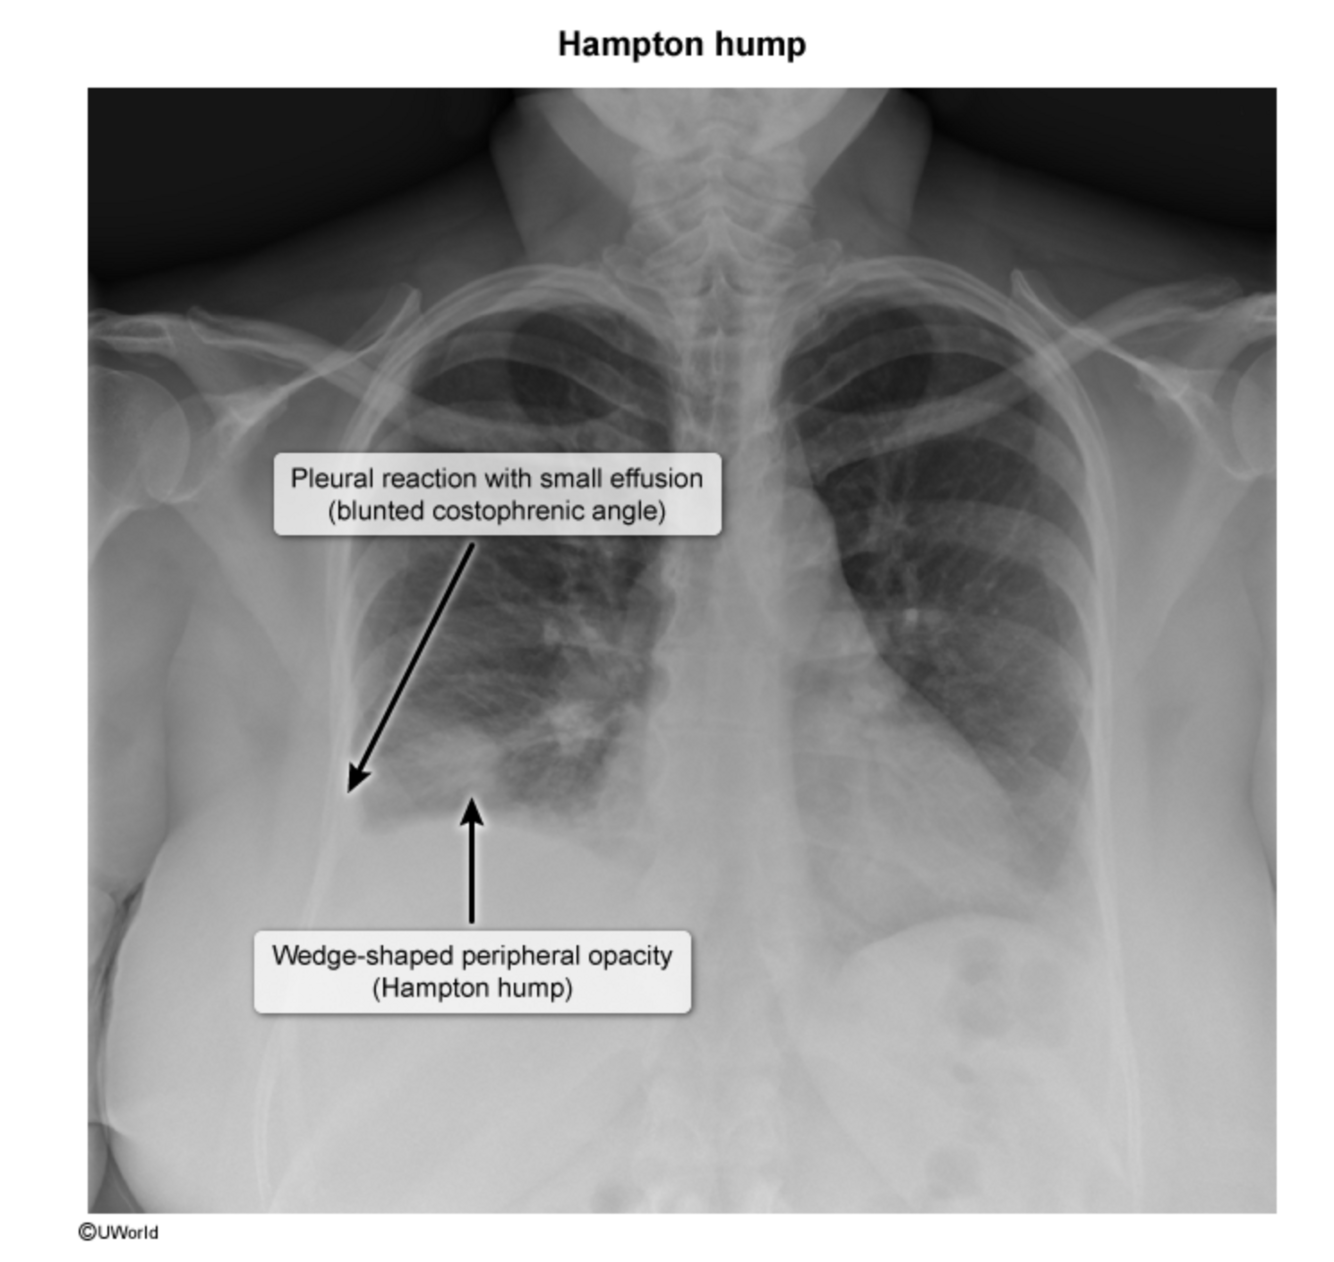

What are some clinical clues seen on CXR that suggest a pulmonary embolism?

Hampton hump. Chest x-ray findings that suggest a PE are wedge-shaped opacities and the adjacent blunted costophrenic angles due to reactive or inflammatory pleural effusion.